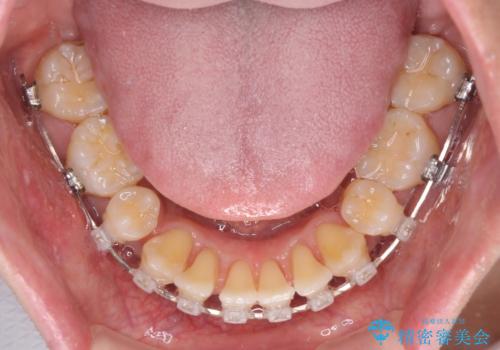

叢生が強い場合、抜歯スペースが叢生を解消するために消費されるため、口元の突出感があまり改善されないことがあります。

今回の治療では、奥歯が前方に傾斜した歯並びだったため、奥に起き上がることで歯列が後方に移動し、横側からも口元が引っ込んだ感じが分かるほど改善されました。